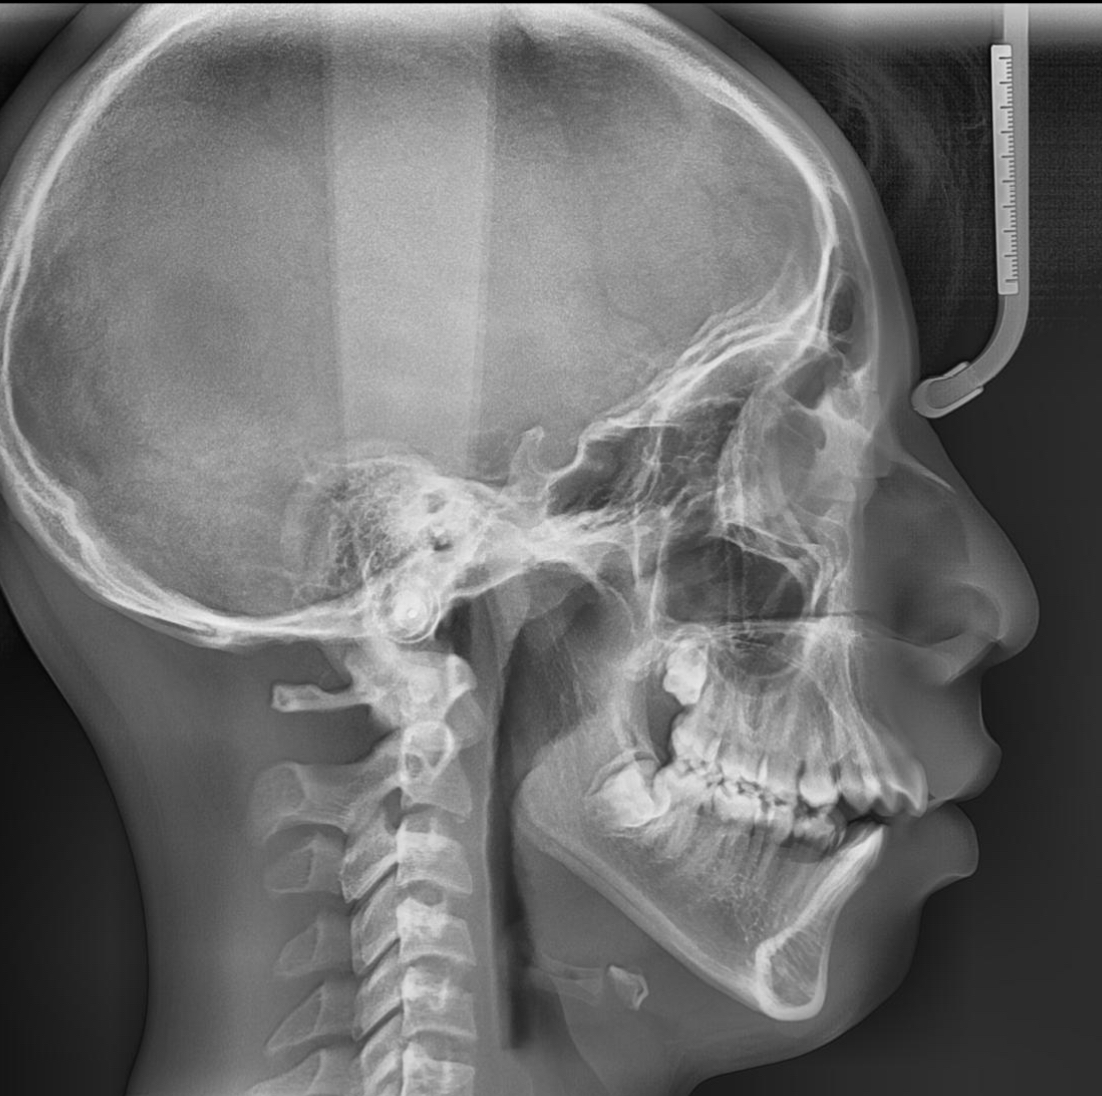

ltn-htn via double jaw surgery dowgrafting + ccw